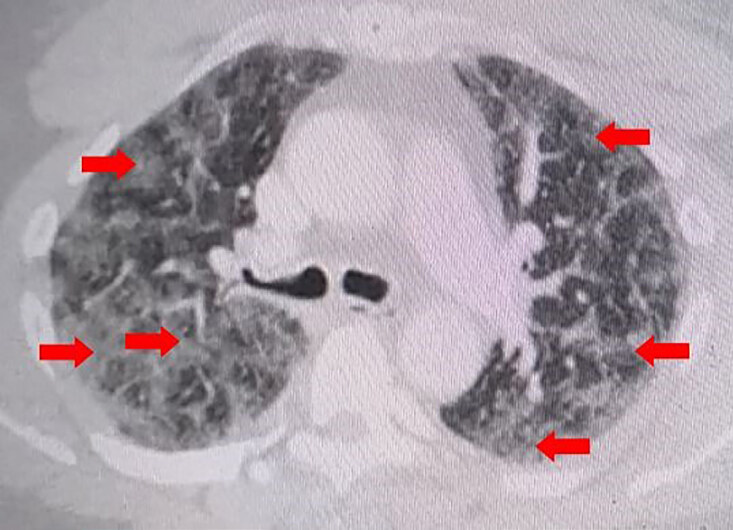

Figure 3. Компьютерная томографическая ангиография грудной клетки с внутривенным контрастированием в поперечном разрезе демонстрирует умеренное, рассеянное, диффузное воспаление легких и интерстициальные образования в легких без тромбоэмболии легочной артерии, как показано красными стрелками. Также имеются незначительные подкожные растяжения и эмфизема передней грудной стенки.